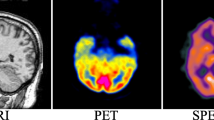

The fusion of multimodal medical images has garnered painstaking attention for clinical diagnosis and surgical planning. Although various scholars have designed numerous fusion methods, the challenges of extracting substantial features without introducing noise and non-uniform contrast hindered the overall quality of fused photos. This paper presents a multimodal medical image fusion (MMIF) using a novel deep convolutional neural network (D-CNN) along with preprocessing schemes to circumvent the mentioned issues. A non-linear average median filtering (NL-AMF) and multiscale improved top-hat (MI-TH) approach are utilized at the preprocessing stage to remove noise and improve the contrast of images. The non-linear anisotropic diffusion (NL-AD) scheme is employed to split the photos into base and detailed parts. The fusion of base parts is accomplished by a dimension reduction method to retain the energy information. In contrast, the detailed parts are fused by novel D-CNN to preserve the enriched detailed features effectively. The simulation results demonstrate that the proposed method produces better brightness contrast and more image details than existing methods by acquiring 0.7649 to 0.8986, 0.3520 to 0.4783, 0.7639 to 0.9056, 68.8932 to 81.0487 gain for quality transfer ratio from source photo to a generated photo (\(Q_{G}^{AB}\)), feature mutual information (FMI), structural similarity index (SSIM), and average pixel intensity (API) respectively.